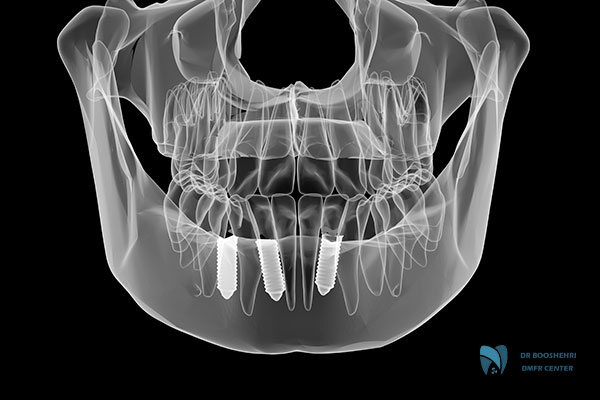

Modern methods for jaw lesion diagnosis include a variety of techniques, each contributing to increased diagnostic accuracy and speed. The use of digital technologies such as Cone Beam Computed Tomography (CBCT) is one of these methods, providing precise three-dimensional images of the jaw structures. Compared to traditional imaging, these methods offer higher accuracy and enable more precise diagnoses.

Additionally, the use of oral imaging techniques such as panoramic radiography and sialography plays a key role in jaw lesion diagnosis. These techniques not only help identify lesions but can also provide comprehensive information about the location and size of the lesion. In this context, the use of accurate TMJ imaging is also crucial, especially when lesions related to the temporomandibular joint or musculoskeletal problems are involved.

Oral imaging techniques are the primary tools in the process of jaw lesion diagnosis. These methods include both two-dimensional and three-dimensional imaging, each with its specific applications. Panoramic radiography, one of the most widely used methods, provides a comprehensive view of the upper and lower jaws and can assist in identifying issues such as cysts, tumors, and bone changes.

In cases where greater precision is needed, accurate TMJ imaging or CBCT is employed. This method offers high-resolution three-dimensional images, allowing doctors to closely examine the jaw structures. Furthermore, methods such as sialography and MRI can also provide additional information in specific cases.